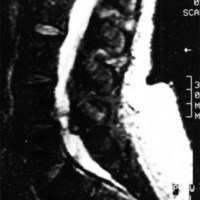

CASO 5

Paciente mujer de 66 años con lumbociatalgia izquierda de 8 meses de evolución. La IRM demostró una lesión yuxtaarticular L4-L5 izquierda isohipointensa en T1 (Fig. 5) y levemente hiperintensa en T2. Se extirpó por vía posterior unilateral. La histología confirmó el diagnóstico de QS.

Fig. 5. Caso 5.